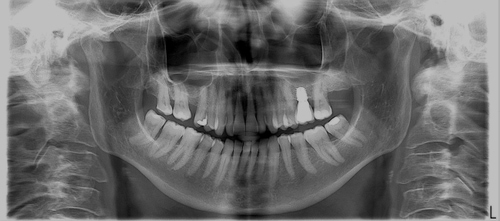

Il nostro studio è provvisto di apparecchio radiografico che esegue Panoramiche e la T.A.C. cone beam Computed Tomography.

Nel nostro studio, il medico odontoiatra, dopo aver diagnosticato, con impronta studio, ortopantomografia e teleradiografia, il tipo di malocclusione, studia e prepara la terapia adatta a correggerla, parla con i genitori ai quali viene spiegata accuratamente la terapia, e solo dopo il consenso degli stessi, inizierà la terapia utilizzando apparecchiature ortodontiche fisse e mobili appropriate.

Un paziente adulto si è presentato nel nostro studio per correggere questa malposizione dei denti dell'arcata superiore ed dell'arcata inferiore. Dopo un attendo studio abbiamo deciso di procedere con la terapia di correzione attraverso l'utilizzo di mascherine trasparenti (F22). Il risultato è stato come noi l'avevamo proposto ed il paziente è rimasto molto soddisfatto del risultato ottenuto. Le foto qui sotto lo testimoniano.

Le foto a sinistra arcata superiore sopra e arcata inferiore sotto prima del trattamento.

Le foto a destra dopo lo studio e il trattamento.

Nelle foto si nota come il trattamento ha corretto in maniera eclatante una malposizione dentale che costringeva il paziente a tenere la bocca chiusa anche quando sorrideva per non vscoprire i denti.